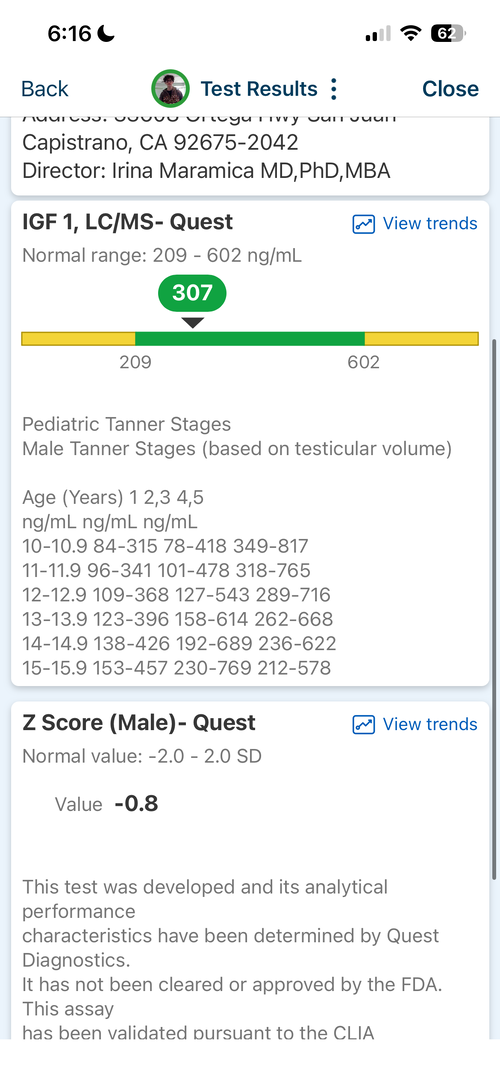

16.6 yr old male at 5'11.1" in height currently. Father is 6'1.5" and Mother is 5'8". I have images of my growth chart along with an X-Ray of my wrist attached. I also attached recent bloodwork tests of TESTOSTERONE, IGF-1 and Cortisol.